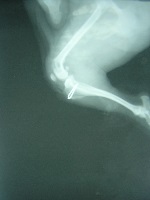

いわゆる膝のさらが正常な位置から内側(内方脱臼)や外側(外方脱臼)にはずれてしまう状態の事をいいます。 小型犬種では内方脱臼が多く、また大型犬種では外方脱臼が多く見られる傾向があります。 この多くは成長期に発生します。原因としては出生時からの膝関節周囲の筋肉や骨などの形成異常、靭帯の付着部の異常などではないかと言われています。 また、打撲や落下などにより強い衝撃が膝関節周囲に加わったときに外傷性の原因で発生したりするとも言われています。 症状としては、程度によりグレードⅠからグレードⅣまで分類されています。 飼い主が気づく症状としては、立ち上がった時は足を上げているが、しばらくすると普通に歩くもしくは、突然キャンといって足を上げるがしばらくすると元に戻るなどさまざまです。 もし、ワンちゃんに異常を感じたら病院にお連れください。 多くは、触診とレントゲン検査にて診断可能です。 治療方法としては、もし症状が繰り返すようなら基本的には外科手術が必要です。 このレントゲンは先日手術したチワワのワンちゃんです。 左が術前の写真で、右が術後の写真です。 当院では膝蓋骨内方脱臼の手術は、基本的に滑車溝の造溝術と脛骨粗面転位術を行っています。 もちろんその他の術式を組み合わせることもあります。 この病気について、気になることがあればお問い合わせください。